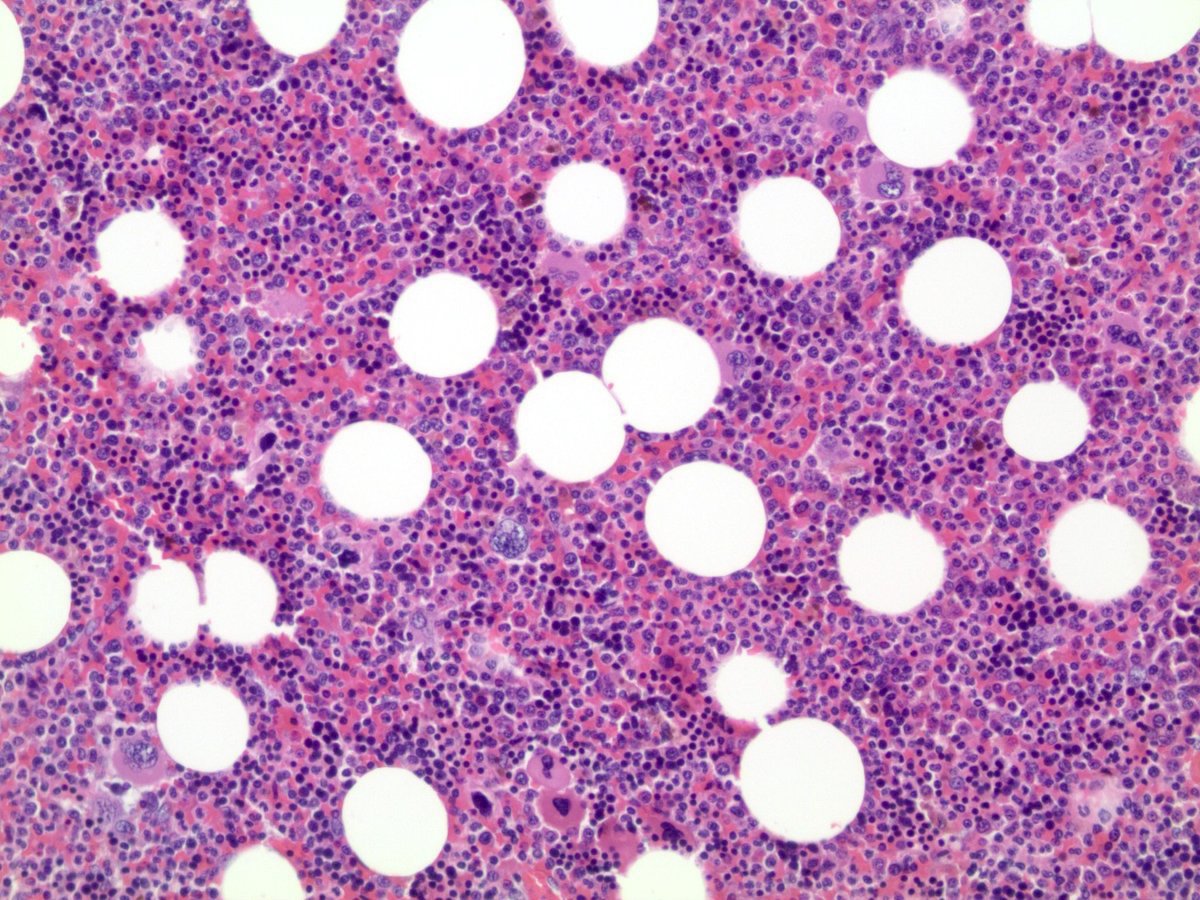

Microscopic (histologic) description

- Mixture of mature adipocytes and extramedullary trilineage hematopoietic cells with full maturation (similar to a hypercellular bone marrow) but often with a markedly increased number of megakaryocytes (Am J Surg Pathol 2006;30:838)

- Calcification, osseous metaplasia and fibrosis can occur

- Rarely may have areas of fibromyxoid degeneration resembling low grade fibromyxoid sarcoma

- Can develop in combination with adrenal cortical tumors, ganglioneuroma, hibernoma, bilateral macronodular adrenocortical disease and congenital adrenal hyperplasia

Microscopic (histologic) images

Contributed by Debra L. Zynger, M.D., Anil Parwani, M.D., Ph.D., O. Hans Iwenofu, M.D., Ph.D. and @ThatGlassTho on Twitter